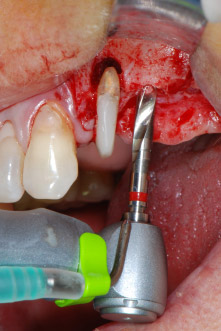

En primer lugar, en un intento por gestionar el problema endo-periodontal, el resto de la superficie radicular se desbridó con cuidado con un equipo piezoeléctrico (Piezomed de W&H, utilizado con el inserto S1 con forma de espátula, concebido en un principio para la erosión de la pared lateral del seno) (figura 4). A continuación, el ápice se erosionó con el mismo instrumento para eliminar el tejido apical infectado residual y reducir las posibles ramificaciones accesorias del canal radicular (apicectomía) (figura 5). No fue necesario realizar un retrorellleno, puesto que la obturación ortógrada se acababa de revisar.

Elevación del seno maxilar y colocación del implante

Antes de colocar el implante, el tejido infectado del hueso alveolar ubicado en el lugar del implante y alrededor de los dientes del pilar se retiró con un inserto concebido en un principio para modelar huesos y recoger virutas óseas: Piezomed y el inserto B5 (figuras 6 y 7).

En el siguiente paso, los lechos del implante se prepararon en las posiciones 25 y 26 con instrumentos rotatorios, utilizando un contra-ángulo con un coeficiente de transmisión de 20:1 (WS-75 L, W&H), junto con el nuevo potente motor de implantes Implantmed de W&H (figuras 8 y 19).

La preparación final junto al seno se realizó de nuevo con un inserto piezoeléctrico (Piezomed S2).

Selección del equipo quirúrgico

Gracias a su acción precisa y suave, tanto el desbridamiento periodontal como la apicectomía de la pieza dental 24 se realizaron utilizando una unidad piezoeléctrica (Piezomed - W&H). Con el fin de evitar el riesgo de perder el diente, se necesitó una limpieza minuciosa, pero sin ejercer demasiada presión. El equipo también resultó útil para el desbridamiento del sitio quirúrgico, que funciona muy bien con el efecto de cavitación específico y las características de corte de la tecnología.

El lecho del implante se preparó con el nuevo motor de implantes Implantmed de W&H, en combinación con un contra-ángulo específicamente diseñado para cirugía oral e implantología.

El coeficiente de transmisión de 20:1, junto con el alto torque de hasta 6,2 Ncm del motor de implantes, permite una preparación a baja velocidad, así como la inserción del implante y el corte de roscas. La preparación final hasta la membrana del seno se realizó de nuevo con la unidad piezoeléctrica y un inserto de diamante redondo (Piezomed S2 de W&H).